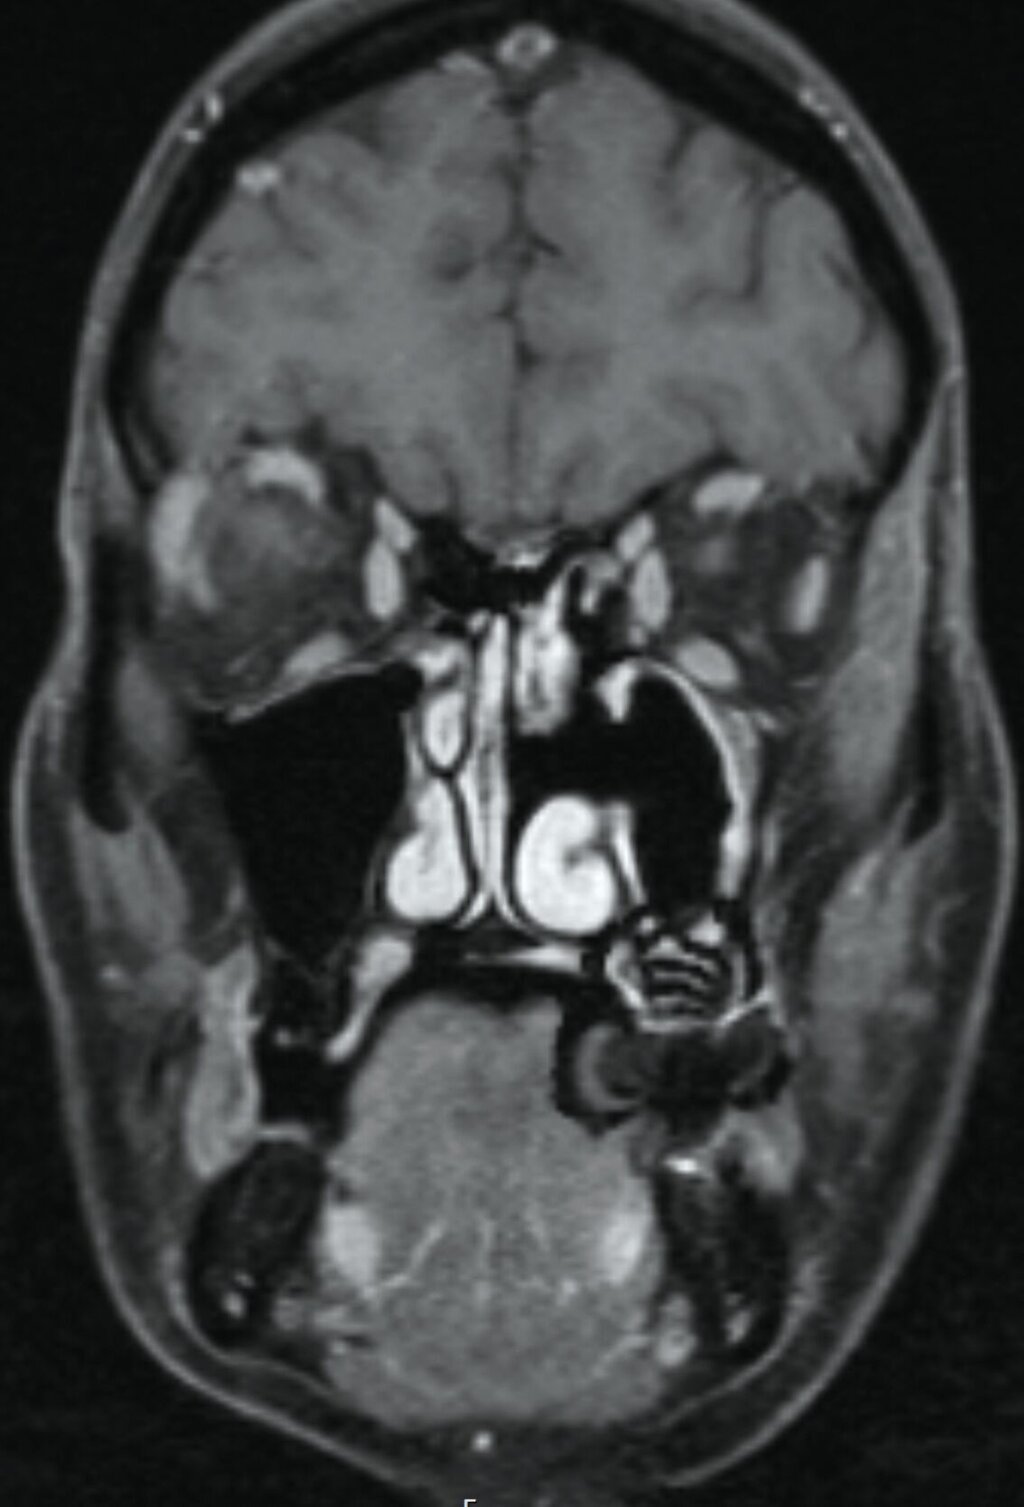

Im Verlauf stellte sich die Patientin trotz stringent eingehaltener Medikation mit erneut verstärkten Schmerzepisoden vor. Die Patientin assoziierte dies mit im Bereich der Kiefer – infolge einer im Vorfeld erfolgten Operation – vorhandenem Osteosynthesematerial zur Re-Fixierung des Kieferhöhlendeckels alio loco. Dies war von eitrigem Ausfluss aus der linken Nase begleitet. In der erweiterten Bildgebung mittels Magnetresonanztomografie zeigte die Patientin eine diffuse Kontrastmittelanhebung des Nervus infraorbitalis bildmorphologisch einer Neuritis entsprechend sowie eine diffuse Kontrastmittelanhebung des kranio-lateralen Kieferhöhlenknochens, teils mit Destruktion der kortikalen Strukturen, was den Verdacht einer Osteomyelitis nahelegte (Abbildung 4). Im zusätzlich angefertigten DVT konnte der Verdacht auf basale Aufhellung des linken Kieferhöhlenbodens bestätigt werden (Abbildung 5). Um eine definitive antimikrobielle Therapie und Diagnosesicherung zu ermöglichen, wurde die Entscheidung zur endoskopischen Probeentnahme gestellt.

Klinisch präsentiert sich ein invertiertes Papillom meist mit Epistaxis, purulentem Ausfluss, Obstruktion der Nasennebenhöhlen oder Kopfschmerzen [Neville, 2009]. Bei ausgedehnten Befunden mit Schädelbasis-Invasion können neurologische Defizite auftreten. Radiologische Befunde sind die meist einseitige Verschattung der Kieferhöhle, die Erosion des Knochens und gegebenenfalls fokale Hyperostosen [Neville, 2009]. Einen besonderen Stellenwert in der Diagnostik hat die Magnetresonanztomografie: Hier können gegebenenfalls „cerebriforme“ Formationen in der kontrastmittelverstärkten T1-Wichtung (contrast enhanced) oder auch in der T2-Wichtung dargestellt werden. Diese Formationen entsprechen der Ursprungslokalisation und vereinfachen damit die Planung einer vollständigen Entfernung – zusätzlich weist ein Verlust von cerebriformen Formationen auf eine Tendenz zur malignen Entartung hin [Ma et al., 2020].